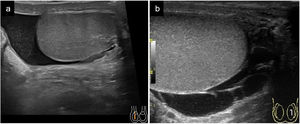

Lesiones extra testicularesHidroceleAcumulación anormal de líquido seroso entre la capa parietal y visceral del escroto dentro de la túnica vaginal, siendo la causa más frecuente de aumento de volumen escrotal indoloro. Puede ser congénito, por cierre incompleto de la túnica vaginal o adquirido, multifactorial: idiopático, infeccioso, traumático o tumoral10,19. Aunque el hidrocele no es una urgencia escrotal aguda, si el volumen del hidrocele es excesivo podría comprometer la viabilidad del testículo. En la mayoría de los casos, la ecografía escrotal nos va a permitir la evaluación inicial y definir la actitud terapéutica a seguir1. En la ecografía se debe separar lo fisiológico de lo patológico, siendo fisiológico 1-2ml de líquido dentro la túnica. Un hidrocele se visualiza como una colección anecogénica con buena transmisión del sonido rodeando la superficie del testículo. La presencia de tabiques puede estar asociada con infección, traumatismo o metástasis, entre otros. La existencia de ecos en su interior suele corresponder a cristales de colesterol o cuerpos de fibrina9,20 (Fig. 5).

HematoceleSe define como la acumulación de sangre entre la capa visceral y parietal del testículo, secundario a procesos como traumatismo, torsión testicular, procesos neoformativos o por intervenciones quirúrgicas21. También pueden cronificar, teniendo como resultado calcificaciones y/o fibrosis. La ecografía muestra áreas focales de ecogenicidad heterogénea rodeando el testículo que, dependiendo de su evolución, podrá presentarse con debris y septos internos1,19.

La rotura testicular se manifiesta como una discontinuidad de la túnica albugínea. También puede existir irregularidad del contorno testicular y ecogenicidad heterogénea con pérdida de la vascularización del parénquima testicular.

En la fractura testicular se detecta solo discontinuidad o rotura del parénquima testicular. A veces se puede identificar una línea hipoecogénica que corresponde a un área avascular en el parénquima testicular, hallazgo que puede asociarse o no a la rotura de la túnica albugínea1,12,14,30,31.